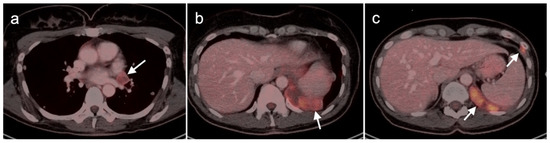

- Gao, Y.-J.; Yang, Z.; Yu, J.-Y.; Li, N.; Wang, X.-J.; Zhou, N.-N. Potential application value of PET/computed tomography in retroperitoneal leiomyosarcoma and a literature review. Nucl. Med. Commun. 2021, 42, 800–810. [Google Scholar] [CrossRef]

- Subramaniam, S.; Callahan, J.; Bressel, M.; Hofman, M.S.; Mitchell, C.; Hendry, S.; Vissers, F.L.; Van der Hiel, B.; Patel, D.; Van Houdt, W.J.; et al. The role of 18 F-FDG PET/CT in retroperitoneal sarcomas—A multicenter retrospective study. J. Surg. Oncol. 2021, 123, 1081–1087. [Google Scholar] [CrossRef]